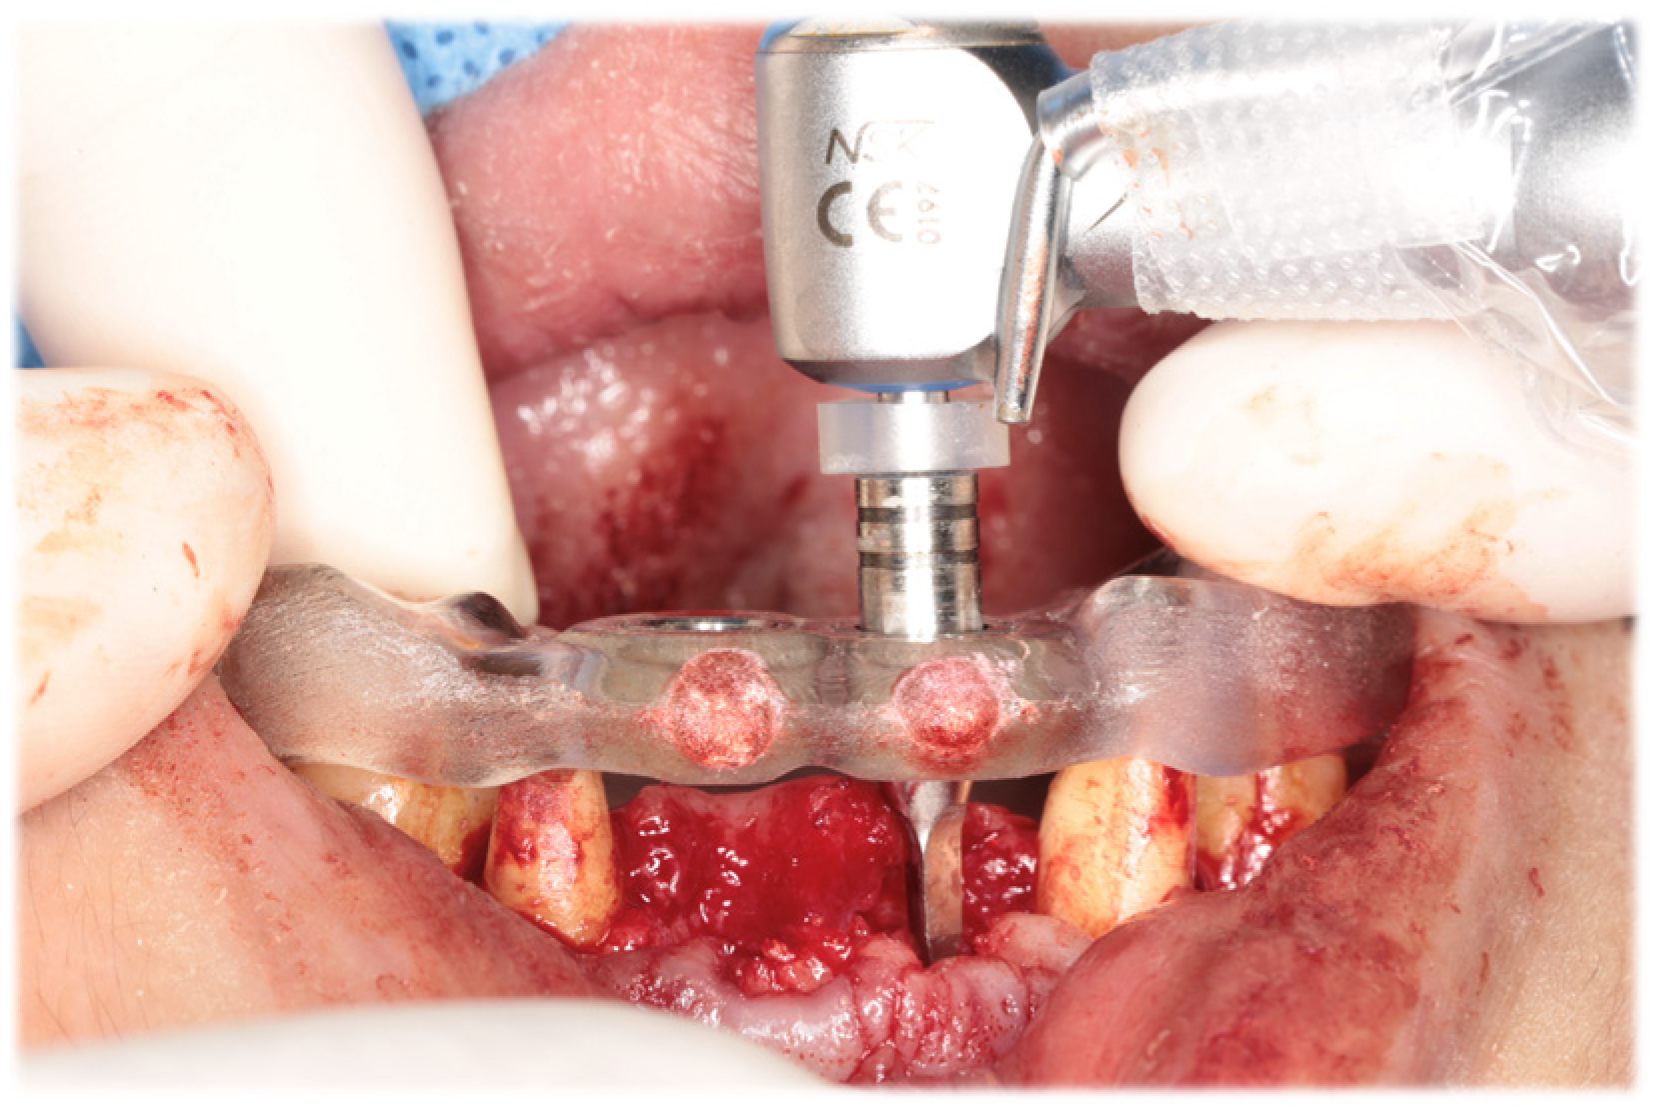

Initial periodontal therapy was begun in February 2016. Concurrently, caries treatment, root canal treatment, and interim prostheses were performed on the maxillary right first molar, mandibular bilateral first molars, and mandibular right second molar. Subsequently, full-mouth scaling and root planing was performed, followed by periodontal tissue regeneration therapy on the maxillary bilateral molars. After the inflammation in periodontal tissues subsided and the occlusal support area was broadened with the interim prosthesis, computer-based simulations were used to assess various options for implant positioning. Prior to the implant placement, a precise plan was created by examining and processing cephalometric and computed tomography scans along with data from intraoral scans. The implant (T3 DCD Tapered Implant, 4/3 × 11.5 mm; BIOMET 3i, Palm Beach, FL, USA) was placed in December 2016 using a surgical guide (Figure 6). Autologous bone and a membrane (Osseoguard; BIOMET 3i) were used in the process of guided bone regeneration to address bone defects (Figure 7). The surgical procedure included making periosteal release incisions followed by primary closure of the operative site. Radiographic images revealed that the implants were positioned parallel to each other, although the implant on the left side was close to the adjacent tooth (Figure 8).

Figure 6. Intraoral photograph during implant placement. A surgical guide was used to place implants in digitally planned locations after extraction of the maxillary bilateral central incisors.